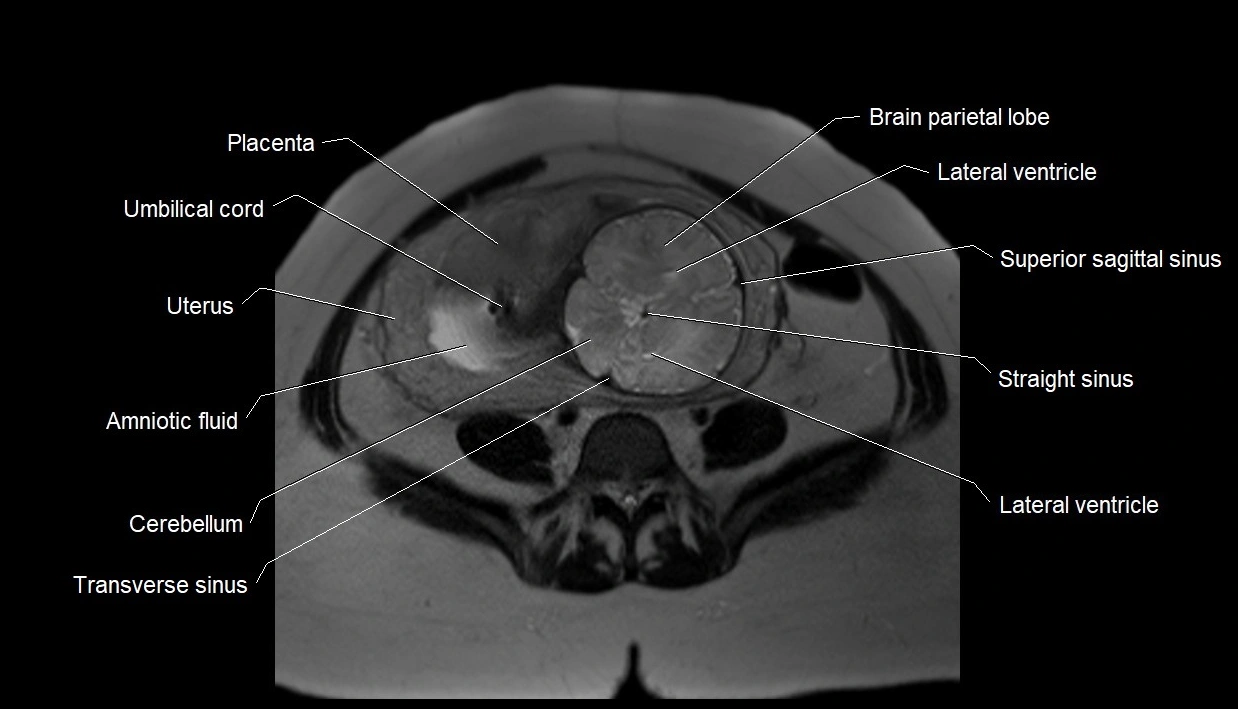

MRI Appearance

T2 HASTE (T2 GRE):

• Amniotic fluid shows very bright hyperintense signal

• Provides natural contrast against fetus and placenta

• Small particles (vernix) may appear as scattered hypointense foci within bright fluid

T1 GRE:

• Amniotic fluid shows low signal intensity (dark)

• Hemorrhage, infection, or proteinaceous content may cause focal or diffuse high signal intensity

MRI image

image